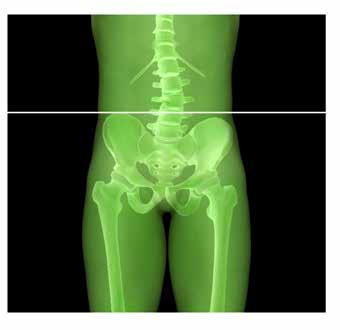

La Bio-Ortodonzia studia la corretta crescita dell’arcata mascellare e mandibolare durante la loro evoluzione. Tale interrelazione è il risultato di un complesso processo dinamico che si esplica dall’infanzia all’età adulta mediante fisiologici cambiamenti, maggiormente evidenti in alcune fasi della dentizione rispetto ad altre; il tutto è correlato alla modalità di crescita delle strutture scheletriche, alle influenze ambientali e al processo di formazione ed eruzione degli elementi dentali. Dalle evidenze scientifiche e cliniche oggi sappiamo che l’equilibrio muscolo-scheletrico dell’apparato stomatognatico condiziona anche l’equilibrio muscolo-scheletrico dell’intero corpo del paziente, in altre parole i disturbi funzionali dell’occlusione, dell’articolazione temporo-mandibolare e dei muscoli masticatori possono provocare disfunzioni in distretti diversi dell’organismo, lontani dalla bocca come la testa, la zona cervicale, la schiena, il bacino, gli arti inferiori e il piede.

Dalle evidenze, scientifca e clinica, oggi sappiamo che l’equilibrio muscolo-scheletrico dell’apparato stomatognatico condiziona anche l’equilibrio muscolo-scheletrico dell’intero corpo del paziente. In altre parole, i disturbi funzionali dell’occlusione, dell’articolazione temporo-mandibolare e dei muscoli masticatori possono provocare disfunzioni in distretti diversi dell’organismo, anche lontani dalla bocca come la testa, la zona cervicale, la schiena, il bacino, gli arti inferiori e il piede. Questi disturbi, in molti casi, sono responsabili di una sintomatologia così dolorosa da compromettere, in parte o completamente, la qualità della vita (Vanini, Cardarelli, D’Arcangelo 2021). La relazione anatomica tra la mandibola e l’osso ioide, attraverso i muscoli sovraioidei e sottoioidei, spiega come la posizione mandibolare possa interferire e condizionare la postura segmentaria del corpo. La mandibola, infatti, infuenza la posizione dell’osso ioide attraverso i muscoli sovraioidei. I muscoli digastrico e stiloioideo vincolano la posizione dell’osso ioide a quella della mandibola e della testa; il muscolo omoioideo, a sua volta, inserendosi sul margine superiore della scapola all’interno

48,49 _ Analisi delle creste iliache: rappresentazione grafica dell’allineamento e del disallineamento.